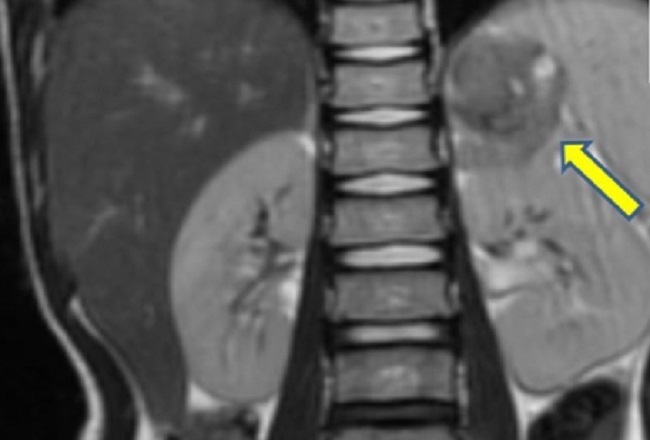

Gambar 1. Neuroblastoma pada Kelenjar Adrenal.

Lokasi predileksi neuroblastoma adalah medulla adrenal. Gejala bervariasi tergantung keterlibatan organ dan penekanan organ sekitar oleh massa tumor. Misalnya, neuroblastoma pada kelenjar adrenal dapat diidentifikasi massa pada pemeriksaan fisik abdomen, sedangkan di area cervical dapat diidentifikasi benjolan pada leher. Keluhan sistemik seperti demam, penurunan berat badan, dan kelelahan dapat menyertai keluhan lokal.

Diagnosis neuroblastoma ditegakkan dengan gambaran histopatologi, yaitu sel bulat kecil berwarna biru pucat atau Homer-Wright pseudorosettes. Pemeriksaan kadar katekolamin dalam urine diperlukan karena produksi berlebihan katekolamin dan metabolitnya pada neuroblastoma. Pencitraan dengan MRI atau CT scan, membantu identifikasi metastasis dan lokasi lesi tumor.[1]